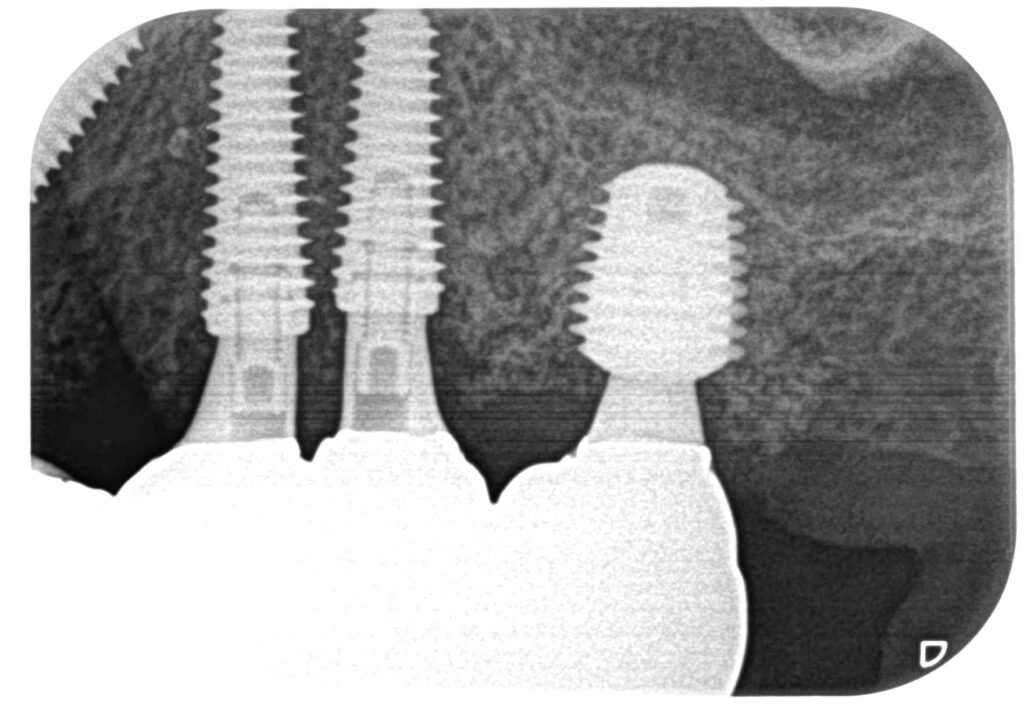

症例240代 女性 主訴 義歯が動いて煩わしい

治療前

治療後

入れ歯だと奥歯しっかり噛めず、取り外しも煩わしいので固定制のインプラントにして欲しいと訴え来院。

左右大臼歯部は、残存骨が1~2㎜程度で骨高が不足している為、ソケットリフト(上顎洞洞底膜挙上術)を行い、インプラントを埋入。口腔内全体で7本のインプラントを埋入。

約4ヶ月の治療期間を経て、全てジルコニアを装着し終了。

リスクとしては外科的侵襲がある。デメリットは、保険外診療の為、経済的負担がある。

費用 381万(税込)(オペ・仮歯・最終補綴物まで含む)